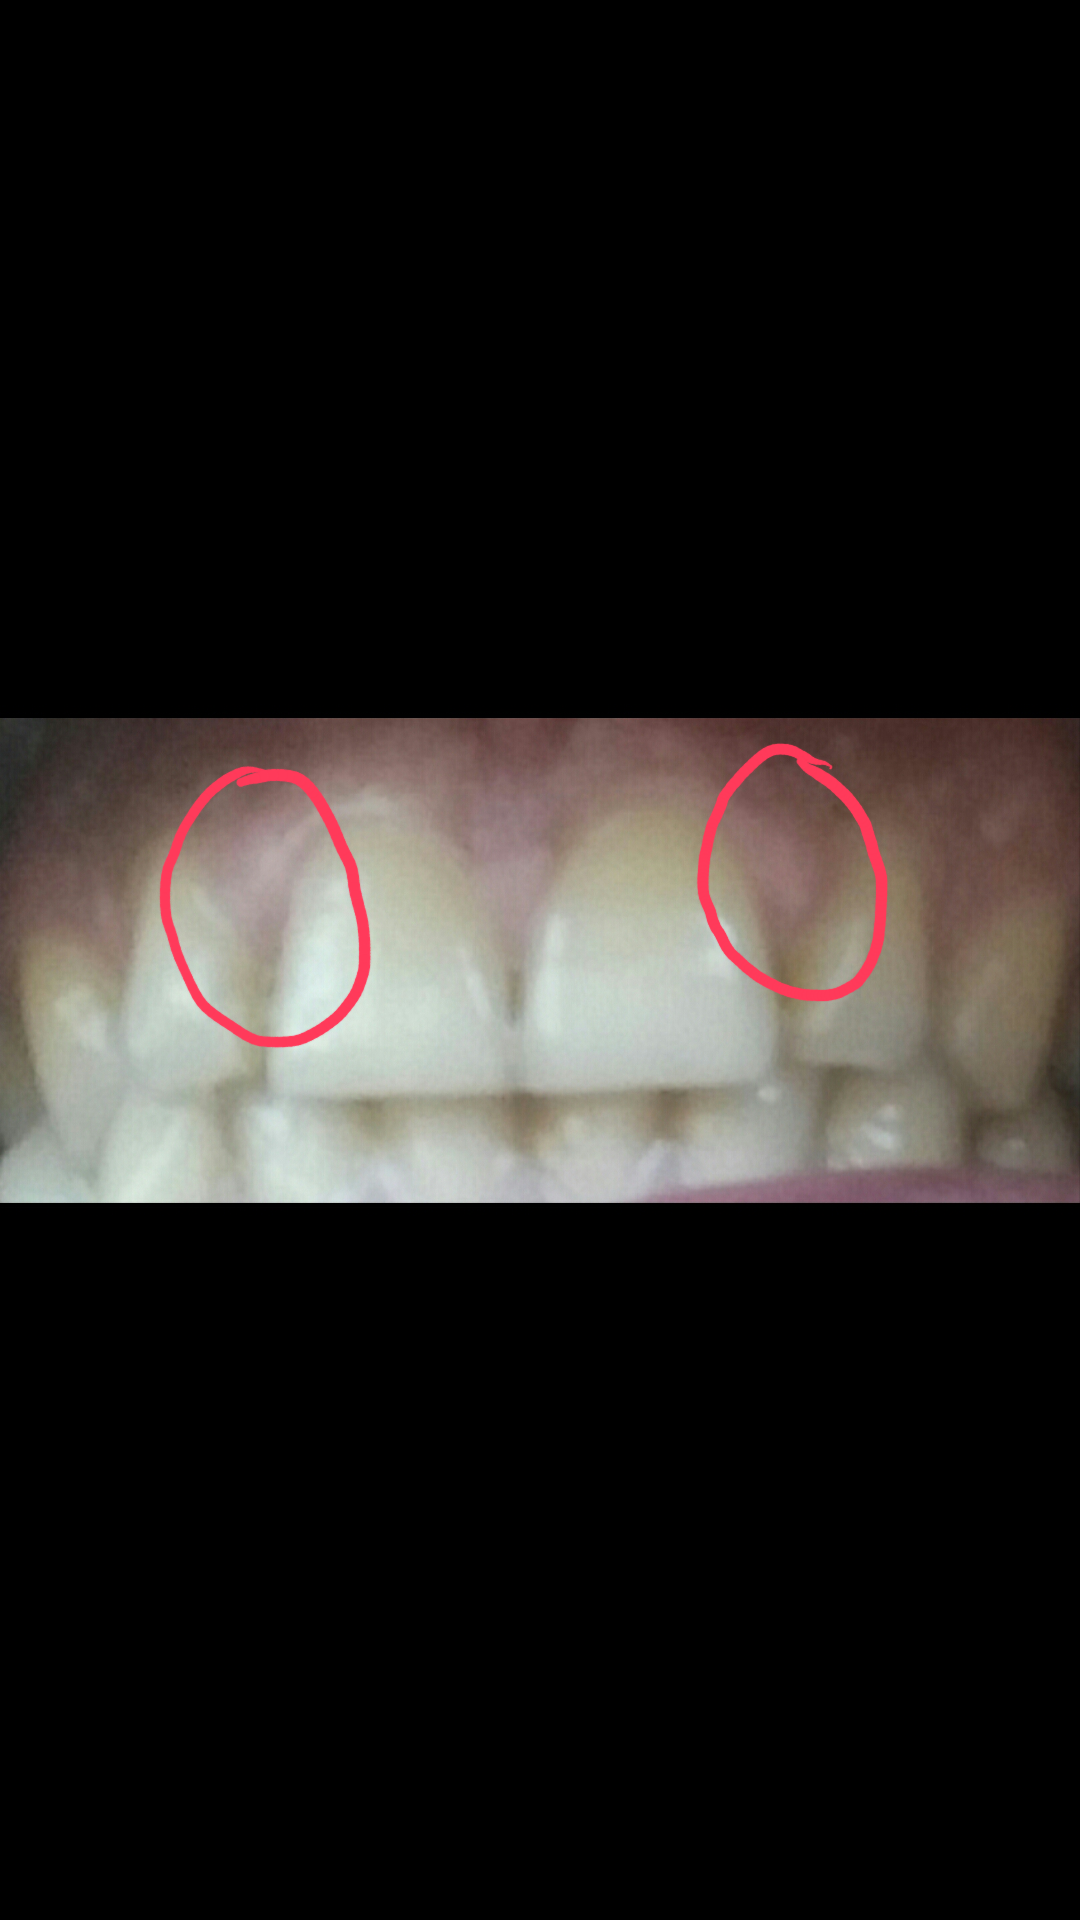

პაროდონტოლოგის კონსულტაცია, ღრძილების დაავადების მკურნალობა და პროფილაქტიკა